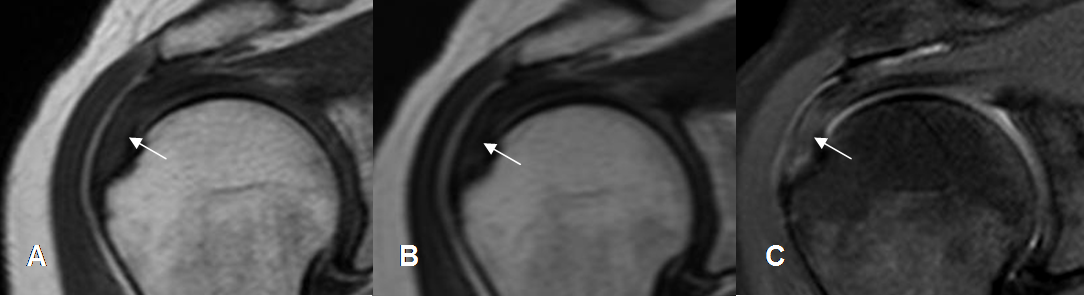

Fig 133. Tendinitis aguda del supraespinoso.

A: RM coronal en T1, B: RM coronal en T2 y C: RM coronal en STIR. Hiperintensidad sobre la inserción del supraespinoso en todas las secuencias, por inflamación aguda.